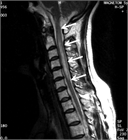

1. MRIのSTIR法は、視神経炎の病態把握に有用で推奨される(推奨度1)

1. 視神経炎の活動性炎症の有無はMRIのT1強調画像脂肪抑制造影で判断する(推奨度1)